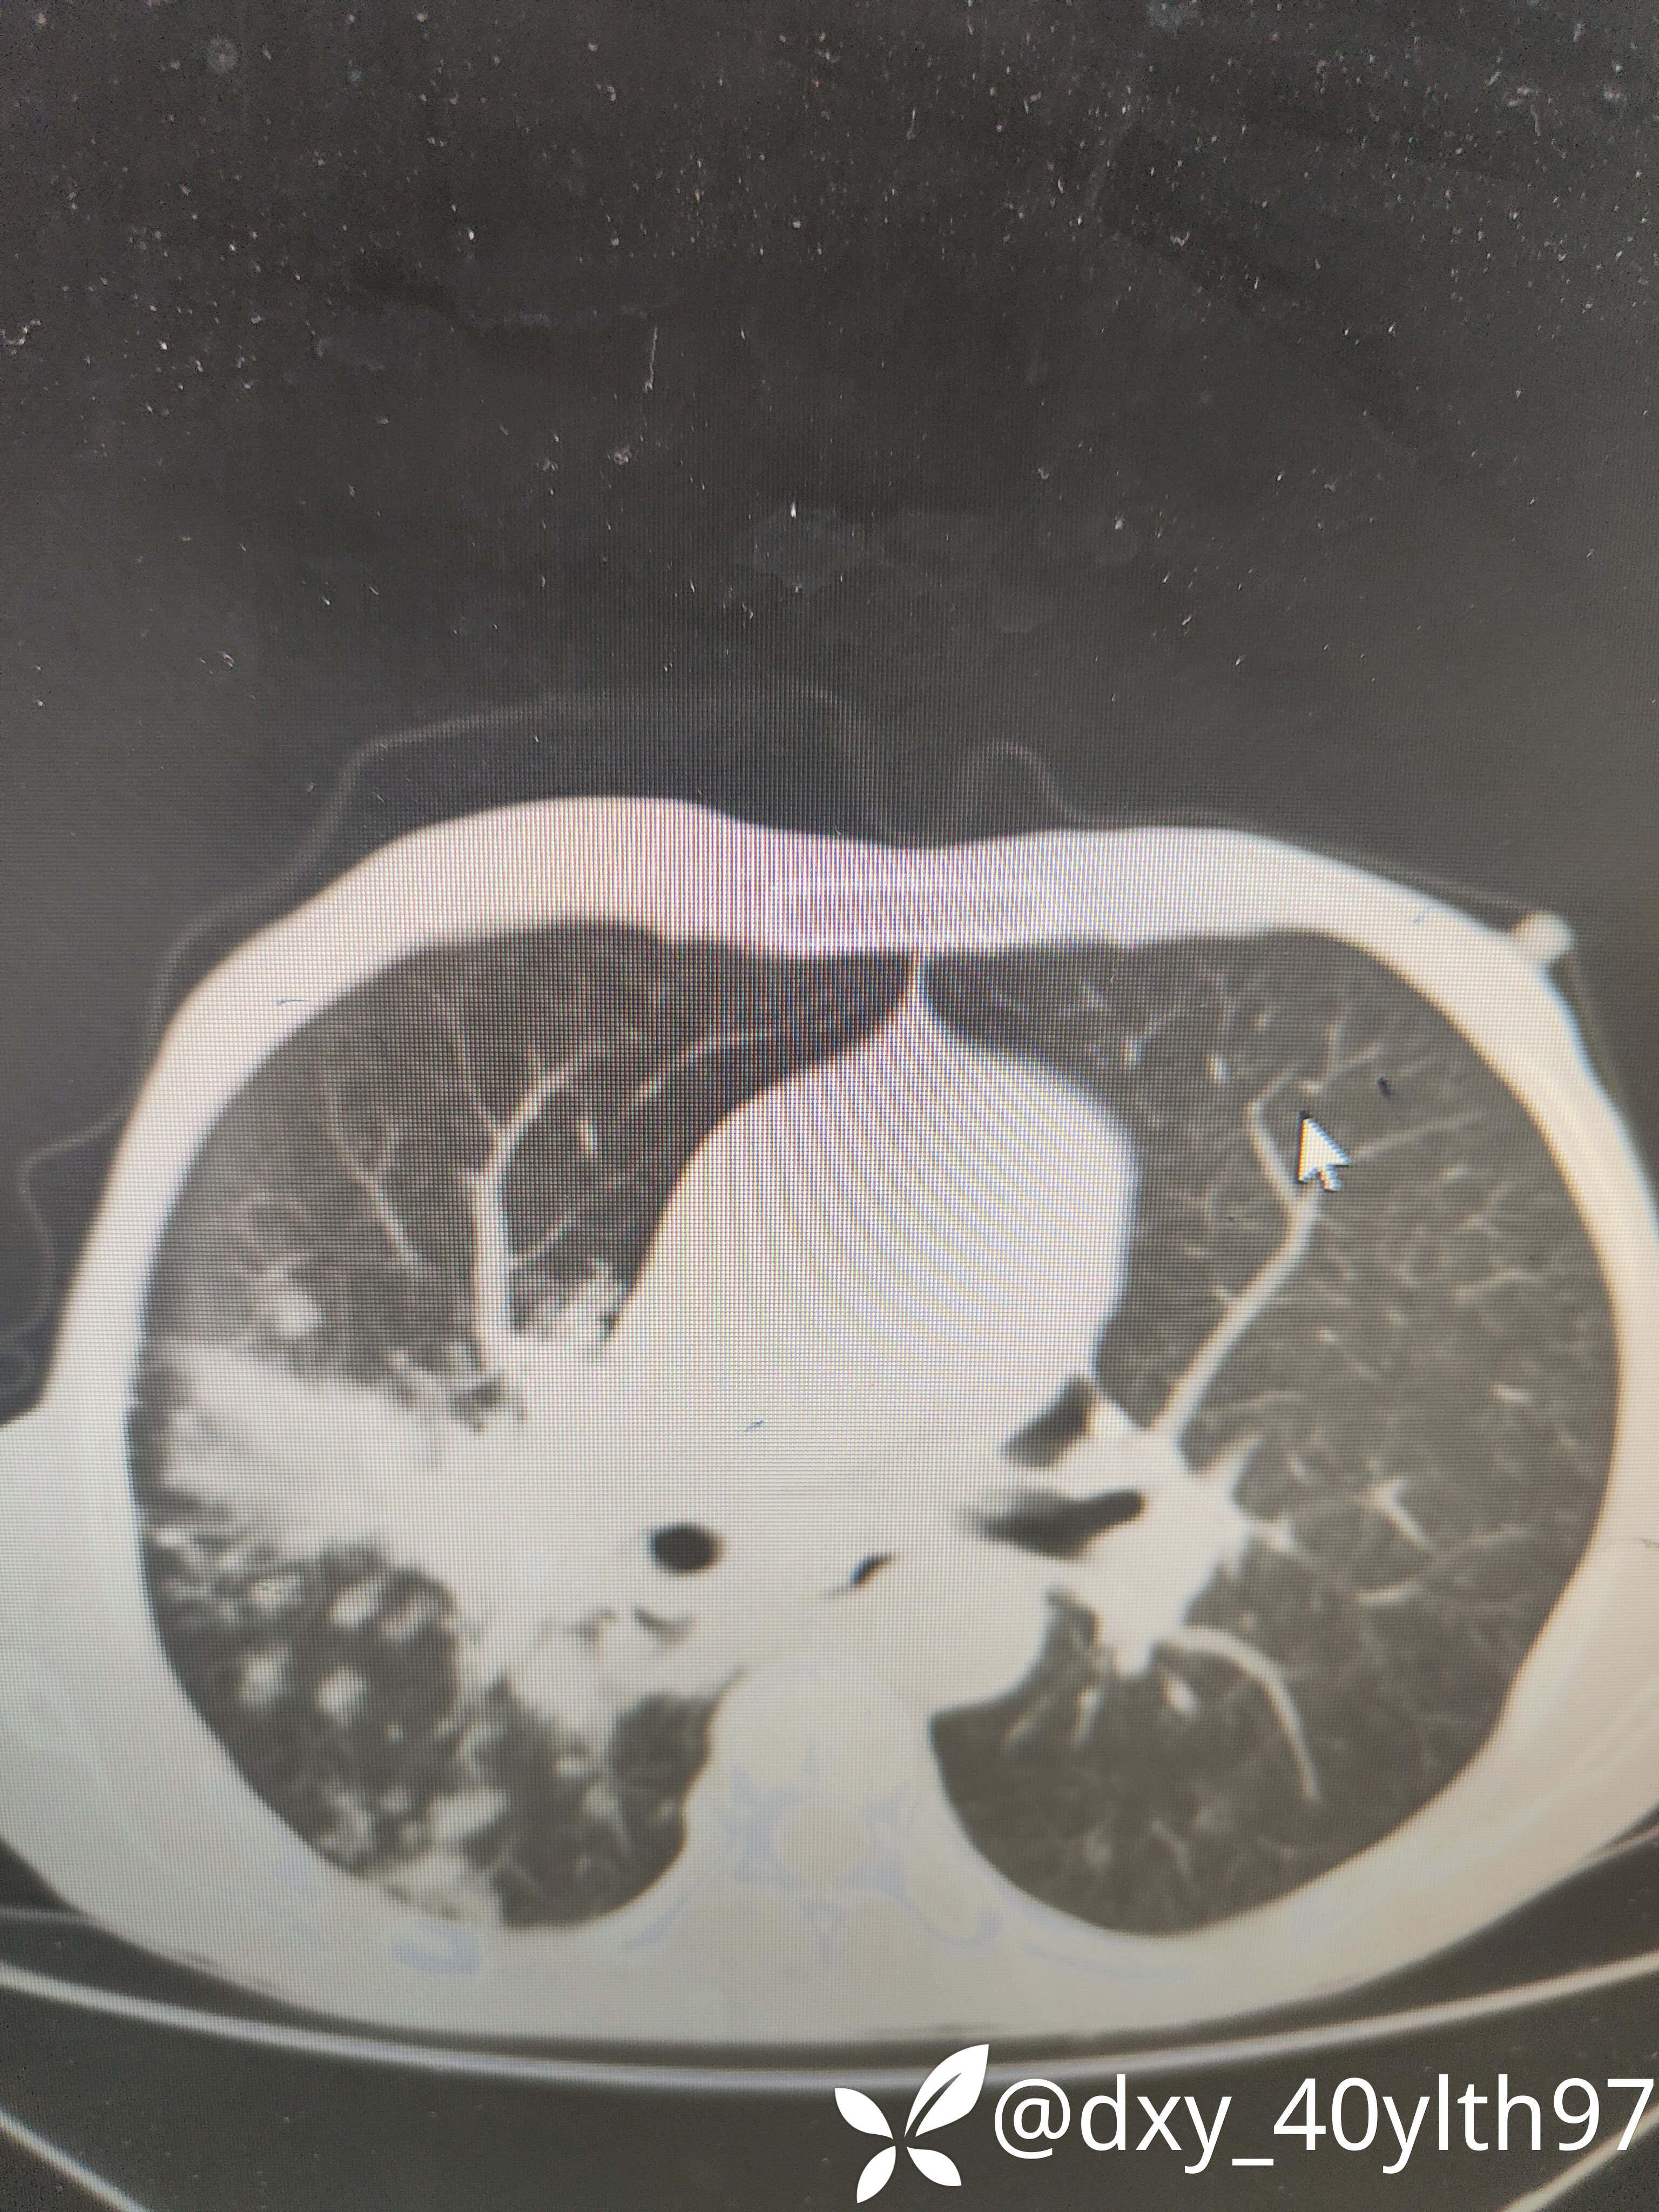

2021年5月首次肺部CT平扫,影像报告提示1.两肺慢性支气管炎、肺气肿、多发肺大疱;2.右肺中下叶多发感染性病变、结节、右肺门增大,建议治疗后复查或进一步检查排查右肺门区肿瘤性病变;3.左肺上段舌叶散在炎性病变

2021年8月因2型糖尿病入院复查肺部CT平扫,影像报告提示:胸部CT复查:1.右肺中下叶感染范围较前相仿、密度增高;2.右肺门区病变较前有所增大;3.右肺外基底段结节较前吸收。

2023年8月肺部CT平扫影像结果提示:1.右肺上叶密度增高影较前显著增大,建议进一步检查;2.两肺多发斑片结节灶较前增多,部分增大。

肺部增强CT影像学提示:右肺内大片不规则影轻度强化,肿瘤可能。